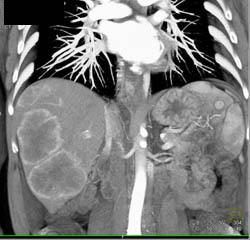

Diagnosis

Hepatoma